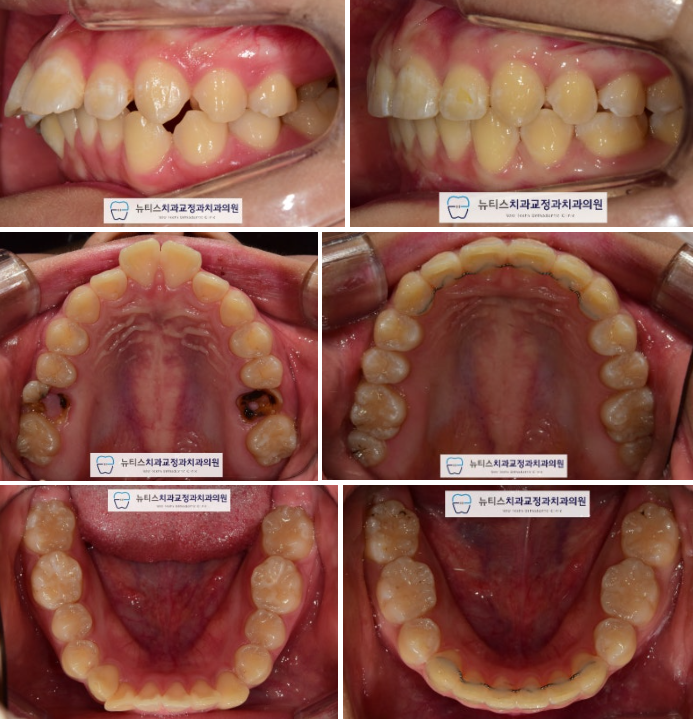

"#ºÎ»ê°á¼ÕÄ¡±³Á¤, #ºÎ»êº¸Ã¶Àü±³Á¤"

Àü ÈÄ ºñ±³»çÁøÀÔ´Ï´Ù.

¿¹Èİ¡ ÁÁÁö ¾Ê¾Æ ¹ßÄ¡ÇØ¾ß ÇÒ Ä¡¾Æ °ø°£À»

¸Þ¿òÀ¸·Î½á ÀÓÇöõÆ®¸¦ ÇÏÁö ¾Ê¾Æµµ µË´Ï´Ù.

¹æ»ç¼± »çÁø¿¡¼µµ º¸½Ã¸é

µ¹ÃâµÈ ¾Õ´Ï°¡ ¾çÈ£ÇØÁø ºÎºÐÀ» º¼ ¼ö ÀÖ½À´Ï´Ù.

(Ä¡·á±â°£ 24°³¿ù)